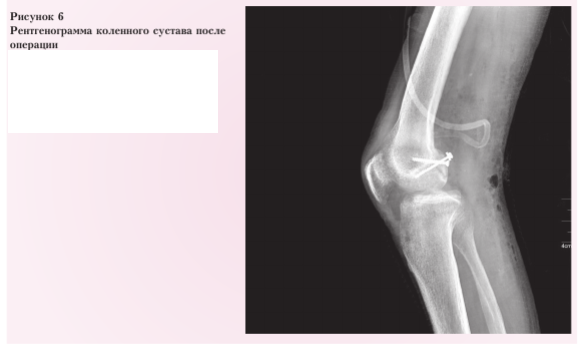

Послеоперационный период протекал без осложнений. Пациент был переведен в Иркутский научный центр хирургии и травматологии. 02.12.2024 задним доступом 15 см обнажена зона перелома заднего края медиального мыщелка бедренной кости. Осколок выделен из рубцов, удален при помощи распатора (рис. 5).

Репонирован, фиксирован двумя кортикальными винтами и резьбовой шайбой. Стояние отломка удовлетворительное (рис. 6). Конечность фиксирована передней гипсовой шиной